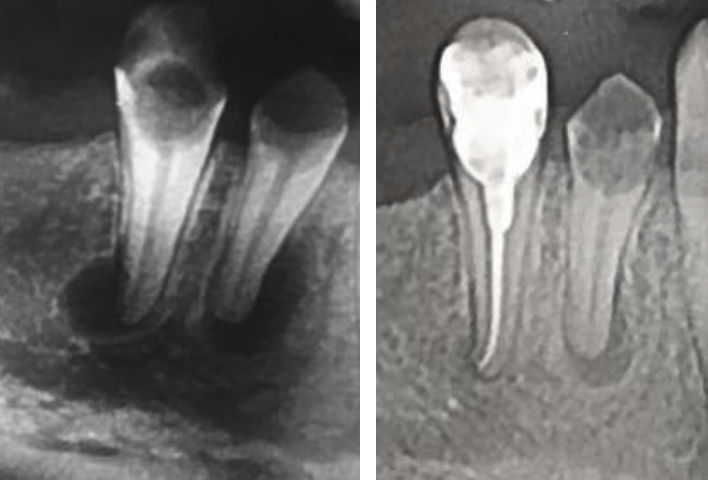

Este greu să ai o părere despre ceva ce nu știi cu exactitate, dar mai ales despre ceva ce nu este vizibil. Pe lângă arhicunoscutele obturații („plombe”), lucrări protetice („dinți falși”), extracții și implanturi, majoritatea pacienților știu doar că în anumite momente trebuie scos nervul; și cam atât. Aici intervenim noi, medicii endodonți, care, în primul rând, trebuie să explicăm cu exactitate și pe înțelesul fiecăruia, ce facem noi exact, care sunt consecințele, alternativele și necesitatea manoperei. Acest dialog este foarte important și nu derulăm tratamentul până când pacientul nu este pe deplin lămurit. Având această abordare, urmărim să scădem reticența pacientului când este vorba de un tratament de canal. Există cazuri extreme în care s-au produs distrucții mari ale osului din jurul vârfului rădăcinii, acestea repetându-se în totalitate după încheierea tratamentului de canal, așa ca în cazul din Fig. 4.4.1.